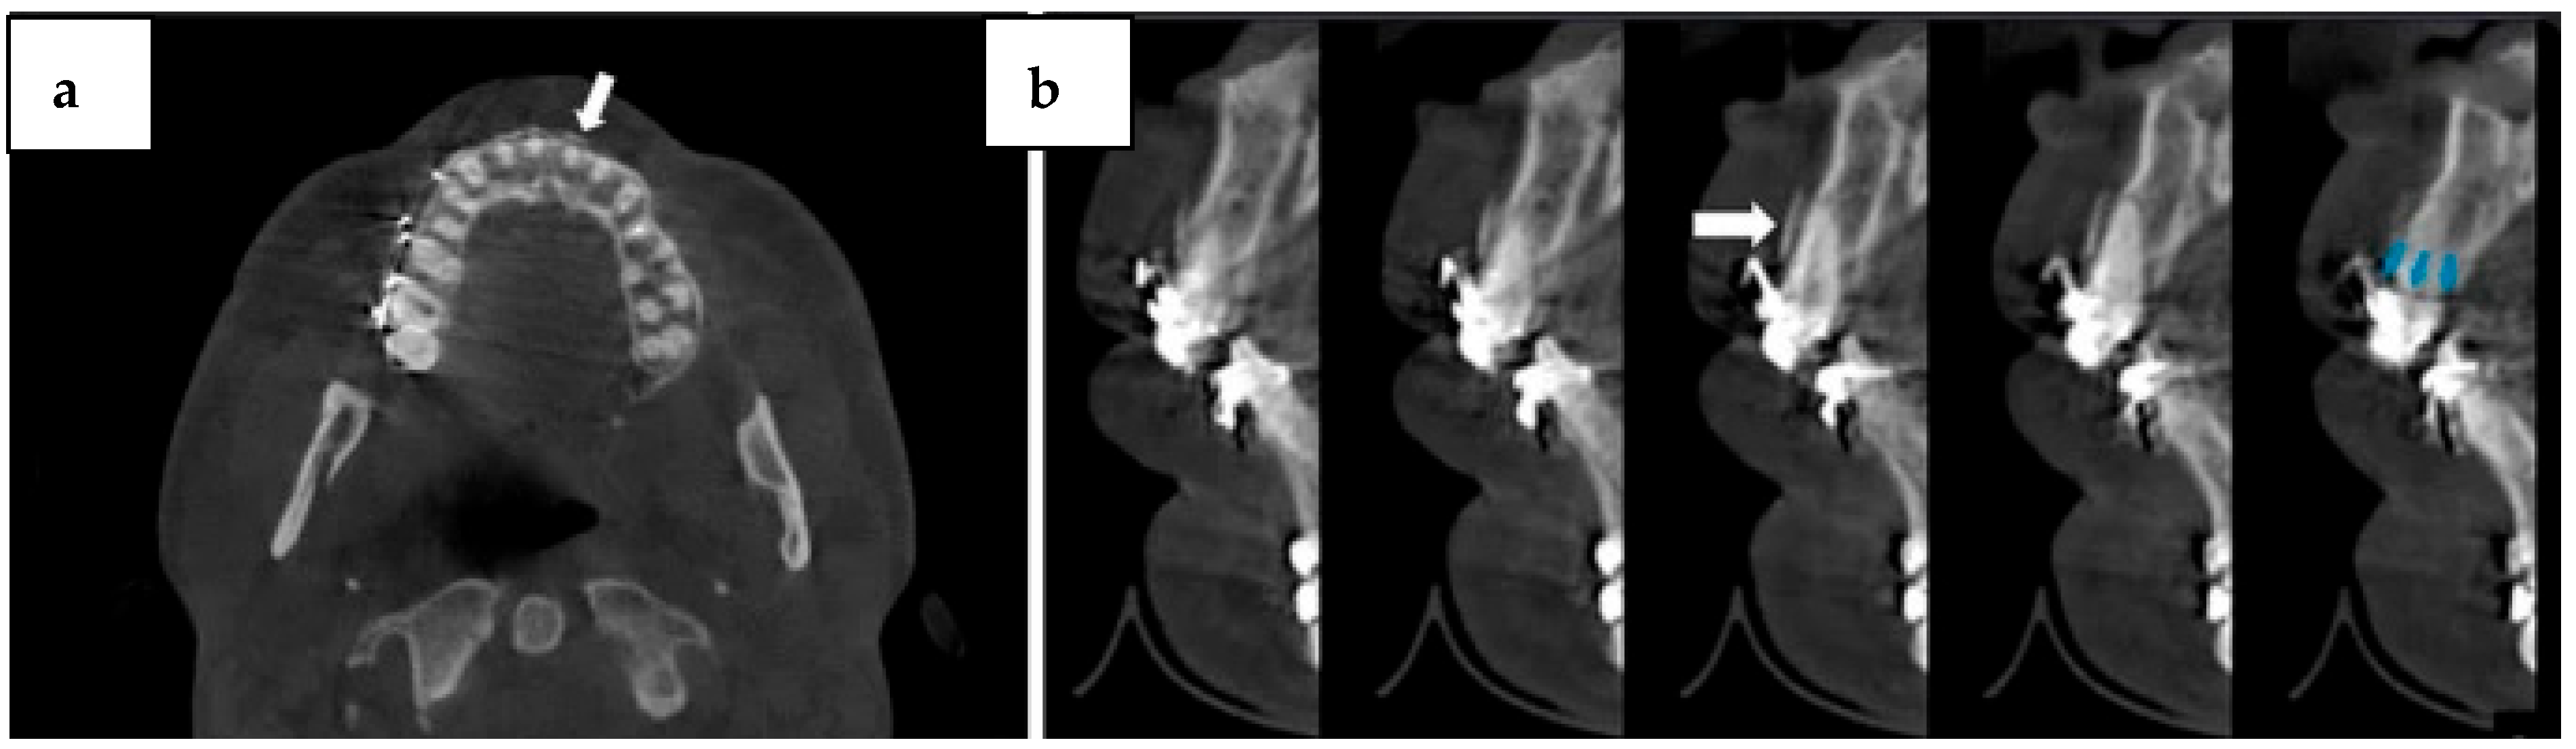

- Yilmaz, S.Y.; Misirlioglu, M.; Adisen, M.Z. A Diagnosis of Maxillary Sinus Fracture with Cone-Beam CT: Case Report and Literature Review. Craniomaxillofacial Trauma Reconstr. 2014, 7, 85–91. [Google Scholar] [CrossRef] [PubMed]

- Yousefi, F.; Shokri, A.; Farhadian, M.; Vafaei, F.; Forutan, F. Accuracy of maxillofacial prototypes fabricated by different 3-dimensional printing technologies using multi-slice and cone-beam computed tomography. Imaging Sci. Dent. 2021, 51, 41. [Google Scholar] [CrossRef] [PubMed]

- Bai, L.; Li, L.; Su, K.; Bleyer, A.; Zhang, Y.; Ji, P. 3D reconstruction images of cone beam computed tomography applied to maxillofacial fractures: A case study and mini review. J. X-ray Sci. Technol. 2018, 26, 115–123. [Google Scholar] [CrossRef]

- Rashid, A.; Feinberg, L.; Fan, K. The Application of Cone Beam Computed Tomography (CBCT) on the Diagnosis and Management of Maxillofacial Trauma. Diagnostics 2024, 14, 373. [Google Scholar] [CrossRef]